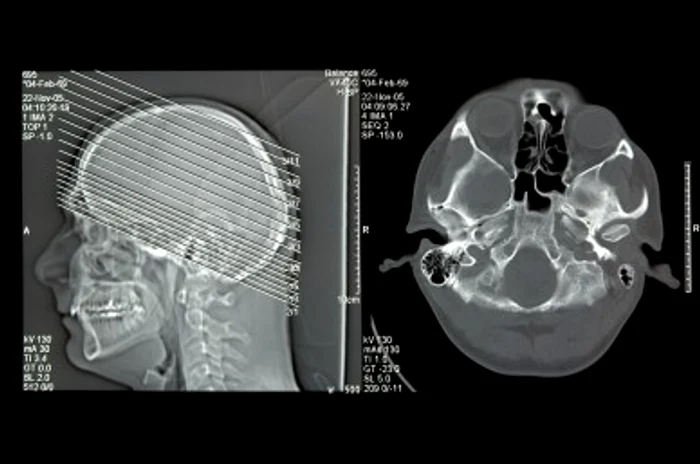

Tumoră cerebrală gigant, operată la privat

Intervenţia a durat 16 ore, din care 15 au fost petrecute la microscop. În cadrul operaţiei de microneochirurgie, realizată la Life Memorial Hospital din Bucureşti s-a folosit aparatură de ultima generaţie.